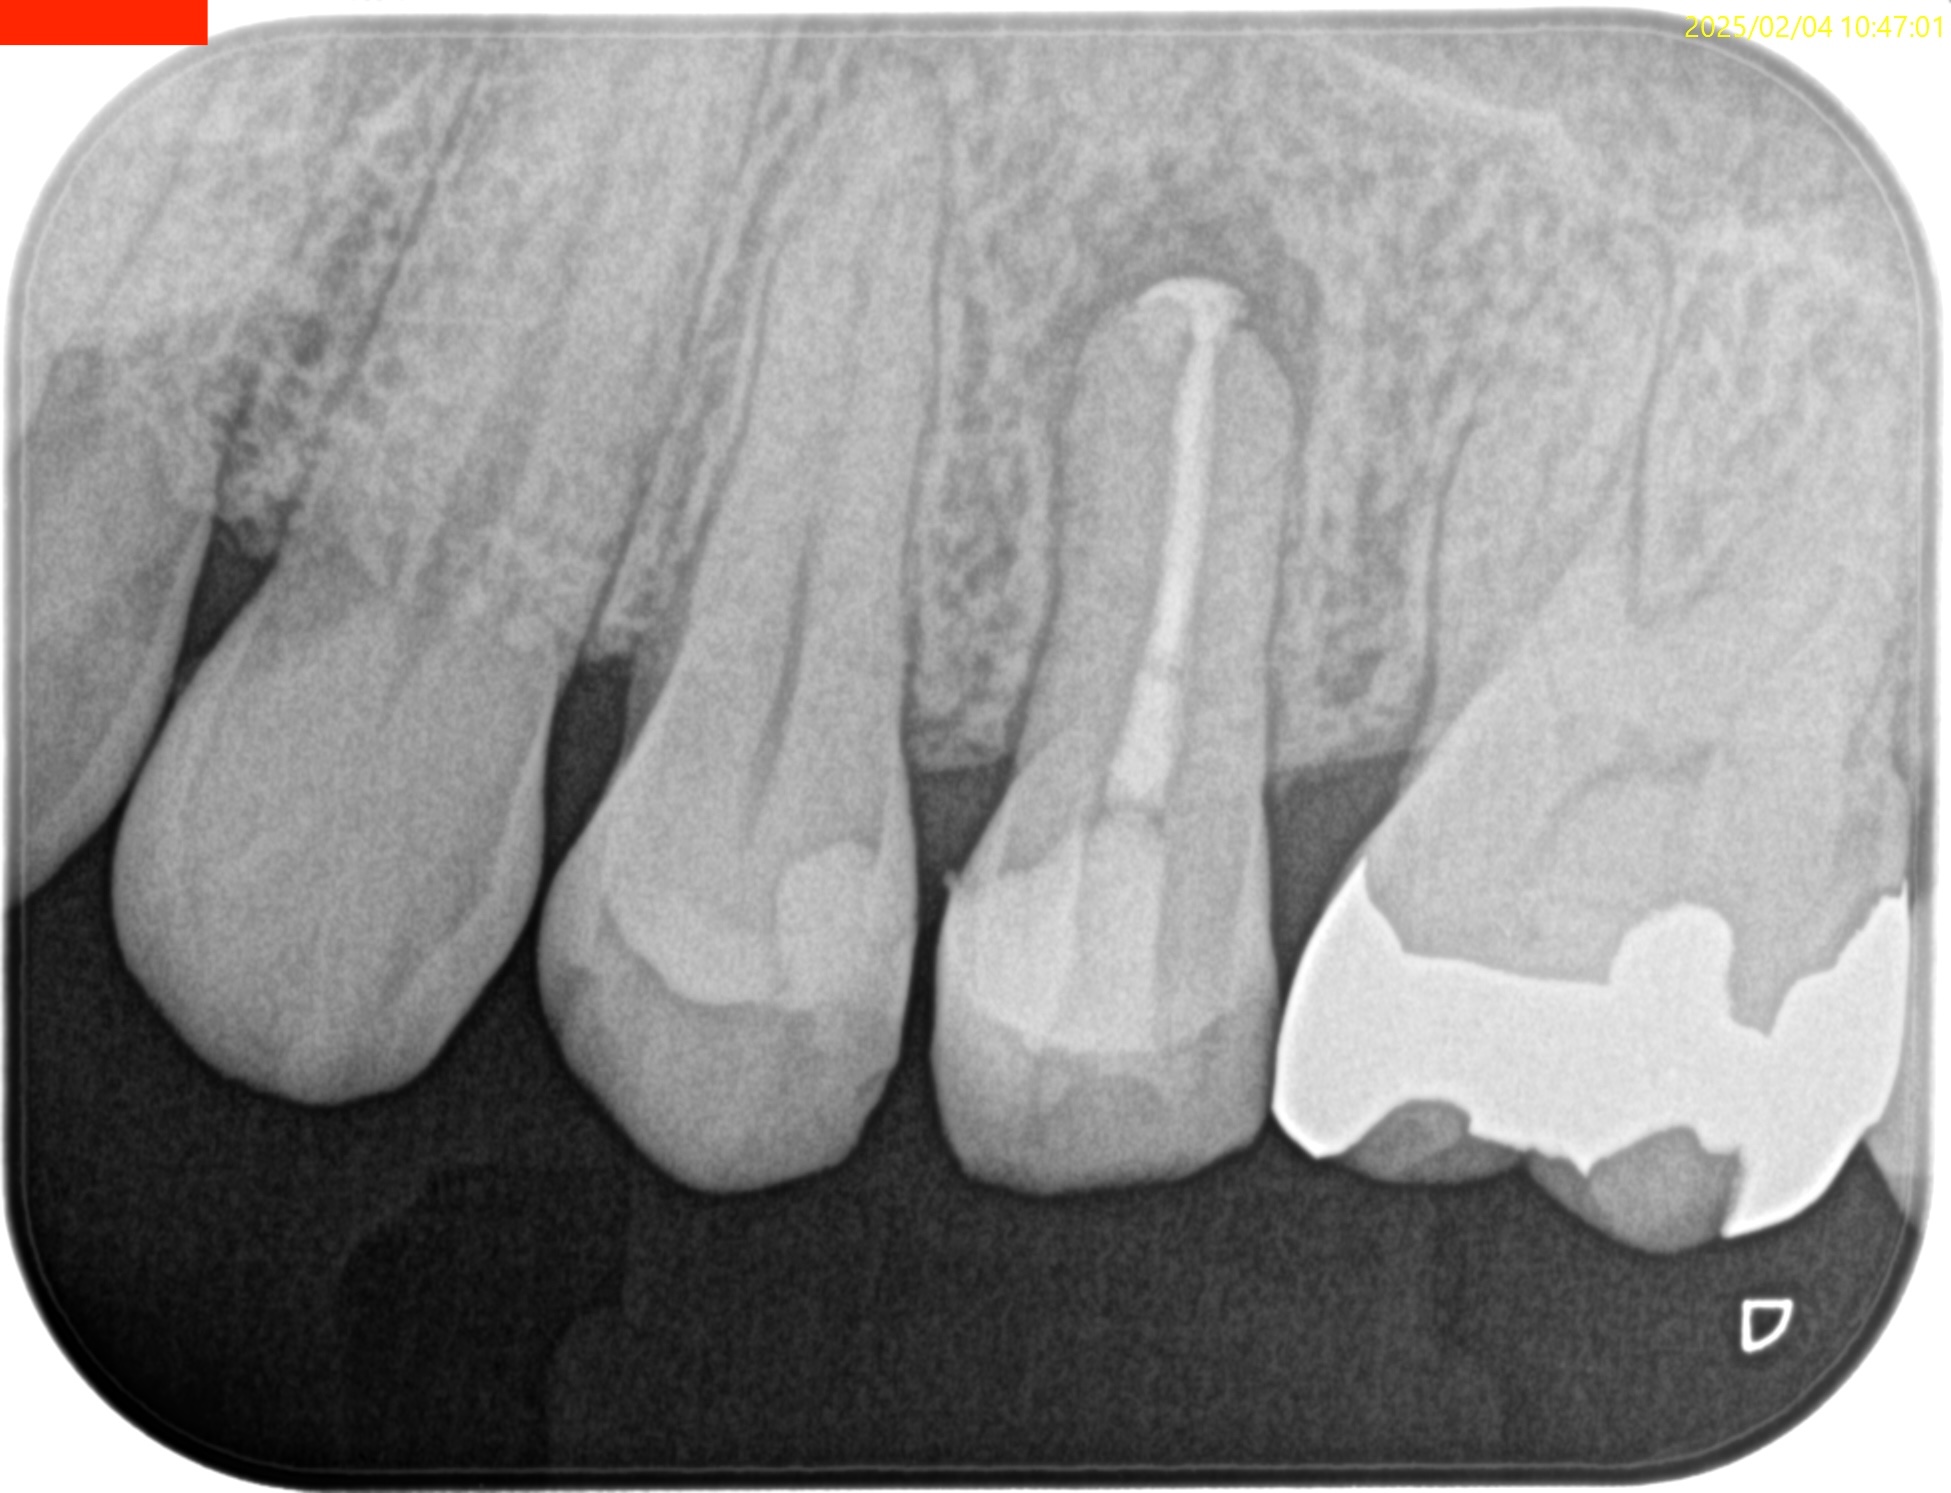

ペリオの問題がない歯だが、PAを撮ると

大きな根尖病変が#13のApex周囲にある。